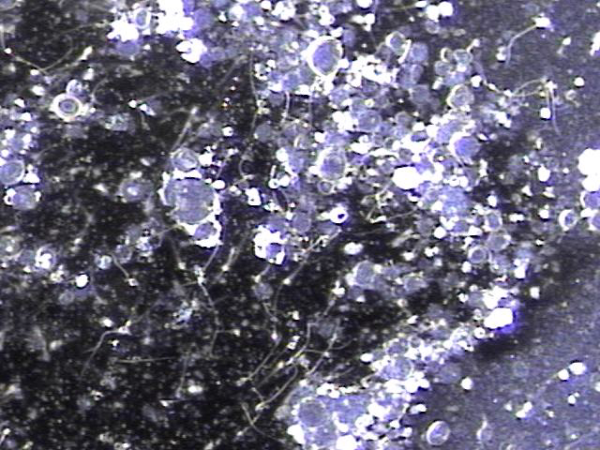

전립선과 정낭과 정관 그리고 사정관 등에서 전립선의 표적 치료후 배양 검사를 하기위해 배출된 결석과 혈정액의 현미경 학적 사진입니다.

Microscopic image of stones and hematospermia discharged from the prostate, seminal vesicles, vas deferens, and ejaculatory ducts following targeted prostate therapy, collected for culture testing.